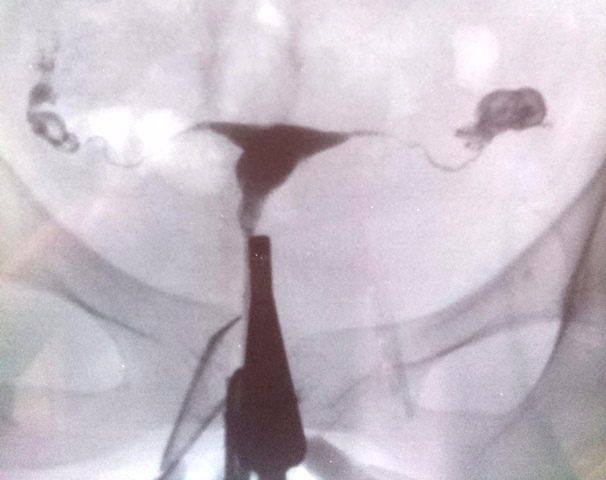

Эхо проходимости труб

Эхо проходимости труб 115 фото